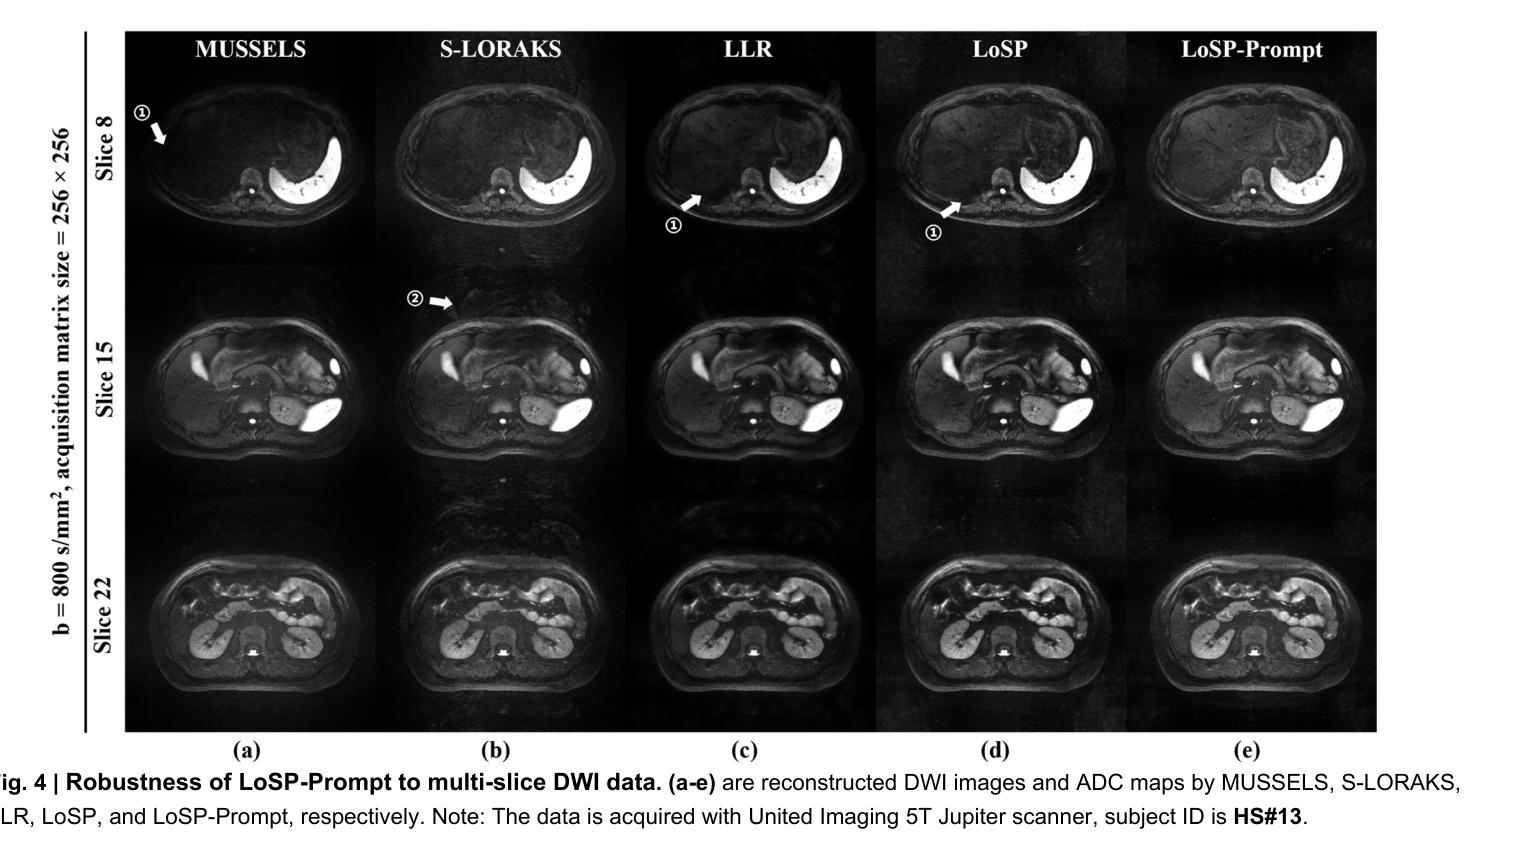

Clinical adoption of multi-shot diffusion-weighted magnetic resonance imaging (multi-shot DWI) for body-wide tumor diagnostics is limited by severe motion-induced phase artifacts from respiration, peristalsis, and so on, compounded by multi-organ, multi-slice, multi-direction and multi-b-value complexities. Here, we introduce a reconstruction framework, LoSP-Prompt, that overcomes these challenges through physics-informed modeling and synthetic-data-driven prompt learning. We model inter-shot phase variations as a high-order Locally Smooth Phase (LoSP), integrated into a low-rank Hankel matrix reconstruction. Crucially, the algorithm’s rank parameter is automatically set via prompt learning trained exclusively on synthetic abdominal DWI data emulating physiological motion. Validated across 10,000+ clinical images (43 subjects, 4 scanner models, 5 centers), LoSP-Prompt: (1) Achieved twice the spatial resolution of clinical single-shot DWI, enhancing liver lesion conspicuity; (2) Generalized to seven diverse anatomical regions (liver, kidney, sacroiliac, pelvis, knee, spinal cord, brain) with a single model; (3) Outperformed state-of-the-art methods in image quality, artifact suppression, and noise reduction (11 radiologists’ evaluations on a 5-point scale, $p<0.05$), achieving 4-5 points (excellent) on kidney DWI, 4 points (good to excellent) on liver, sacroiliac and spinal cord DWI, and 3-4 points (good) on knee and tumor brain. The approach eliminates navigator signals and realistic data supervision, providing an interpretable, robust solution for high-resolution multi-organ multi-shot DWI. Its scanner-agnostic performance signifies transformative potential for precision oncology.

在临床采用多回扩散加权磁共振成像(multi-shot DWI)进行全身肿瘤诊断时,受到呼吸、蠕动等引起的严重运动相位伪影的限制,再加上多器官、多切片、多方向和多b值的复杂性。在这里,我们引入了一种重建框架,名为LoSP-Prompt,它通过物理信息建模和合成数据驱动提示学习来克服这些挑战。我们将不同射击之间的相位变化建模为高阶局部平滑相位(LoSP),并将其集成到低秩Hankel矩阵重建中。关键的是,该算法的秩参数是通过仅使用模拟生理运动的合成腹部DWI数据进行提示学习来自动设置的。在超过10,000张临床图像(43名受试者,4种扫描仪型号,5个中心)的验证中,LoSP-Prompt:(1)实现了临床单发DWI两倍的空间分辨率,提高了肝脏病变的清晰度;(2)使用单一模型推广到七个不同的解剖区域(肝脏、肾脏、骨盆、膝盖、脊髓、大脑);(3)在图像质量、伪影抑制和降噪方面优于最新方法(11名放射科医生在五点量表上进行评估,p<0.05),在肾脏DWI上获得4-5分(优秀),肝脏、骨盆和脊髓DWI上获得4分(良好至优秀),膝盖和肿瘤大脑获得3-4分(良好)。该方法消除了导航信号和真实数据监督,提供了一种可解释、稳健的解决方案,用于高分辨率多器官多回DWI。其扫描仪无关的性能表明对精准肿瘤学具有变革潜力。

Summary

在医学图像领域中,针对体部肿瘤的诊断采用了多站式扩散加权磁共振成像(multi-shot DWI),但由于呼吸、蠕动等引起的严重运动引起的相位伪影限制了其临床应用。为解决此问题,本文提出了一种重建框架LoSP-Prompt,通过物理信息建模和合成数据驱动的提示学习来克服这些挑战。该算法实现了临床单站式DWI的两倍空间分辨率,提高了肝脏病变的辨识度,并在多个解剖区域具有广泛应用性。此外,其在图像质量、伪影抑制和降噪方面均优于现有技术,并在肾脏DWI上取得了卓越表现。此方法无需导航信号和真实数据监督,提供了一种可解释、稳健的高分辨率多站式DWI解决方案,对精确肿瘤学具有变革潜力。

Key Takeaways

1. 多站式扩散加权磁共振成像(multi-shot DWI)在临床应用中受到限制,主要由于运动引起的相位伪影。

2. 提出了一种重建框架LoSP-Prompt,通过物理信息建模和合成数据驱动的提示学习来解决挑战。

3. LoSP-Prompt实现了两倍于临床单站式DWI的空间分辨率,提高了肝脏病变的辨识度。

4. 该方法可在多个解剖区域广泛应用,包括肝脏、肾脏、骨盆、膝盖、脊髓和大脑。

5. LoSP-Prompt在图像质量、伪影抑制和降噪方面表现出卓越性能,优于现有技术。

6. 该方法无需导航信号和真实数据监督,提供了可解释性和稳健性。